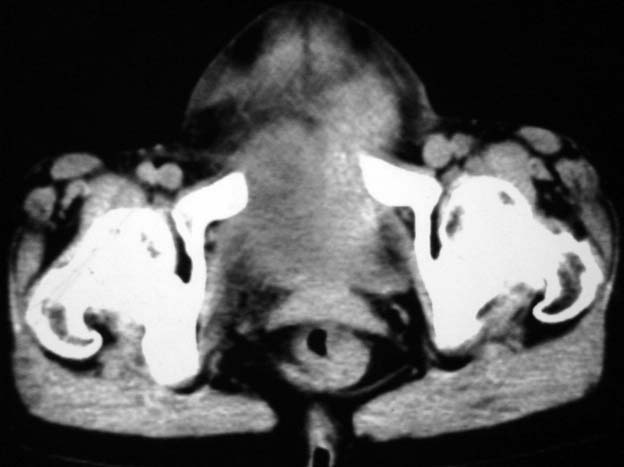

女,75岁,腹部胀大半年余,无其他症状。

考虑来源与卵巢的巨大囊腺瘤或囊肿。

真是腹大如牛,考虑卵巢巨大囊腺瘤或囊肿。

1、考虑卵巢巨大囊腺瘤或囊肿。2、子宫肌瘤不除外。

考虑来源于卵巢的巨大囊腺瘤;如果是单纯囊肿不知其前部的更低密度区怎么解释?

考虑来源卵巢巨大黏液性囊腺瘤。